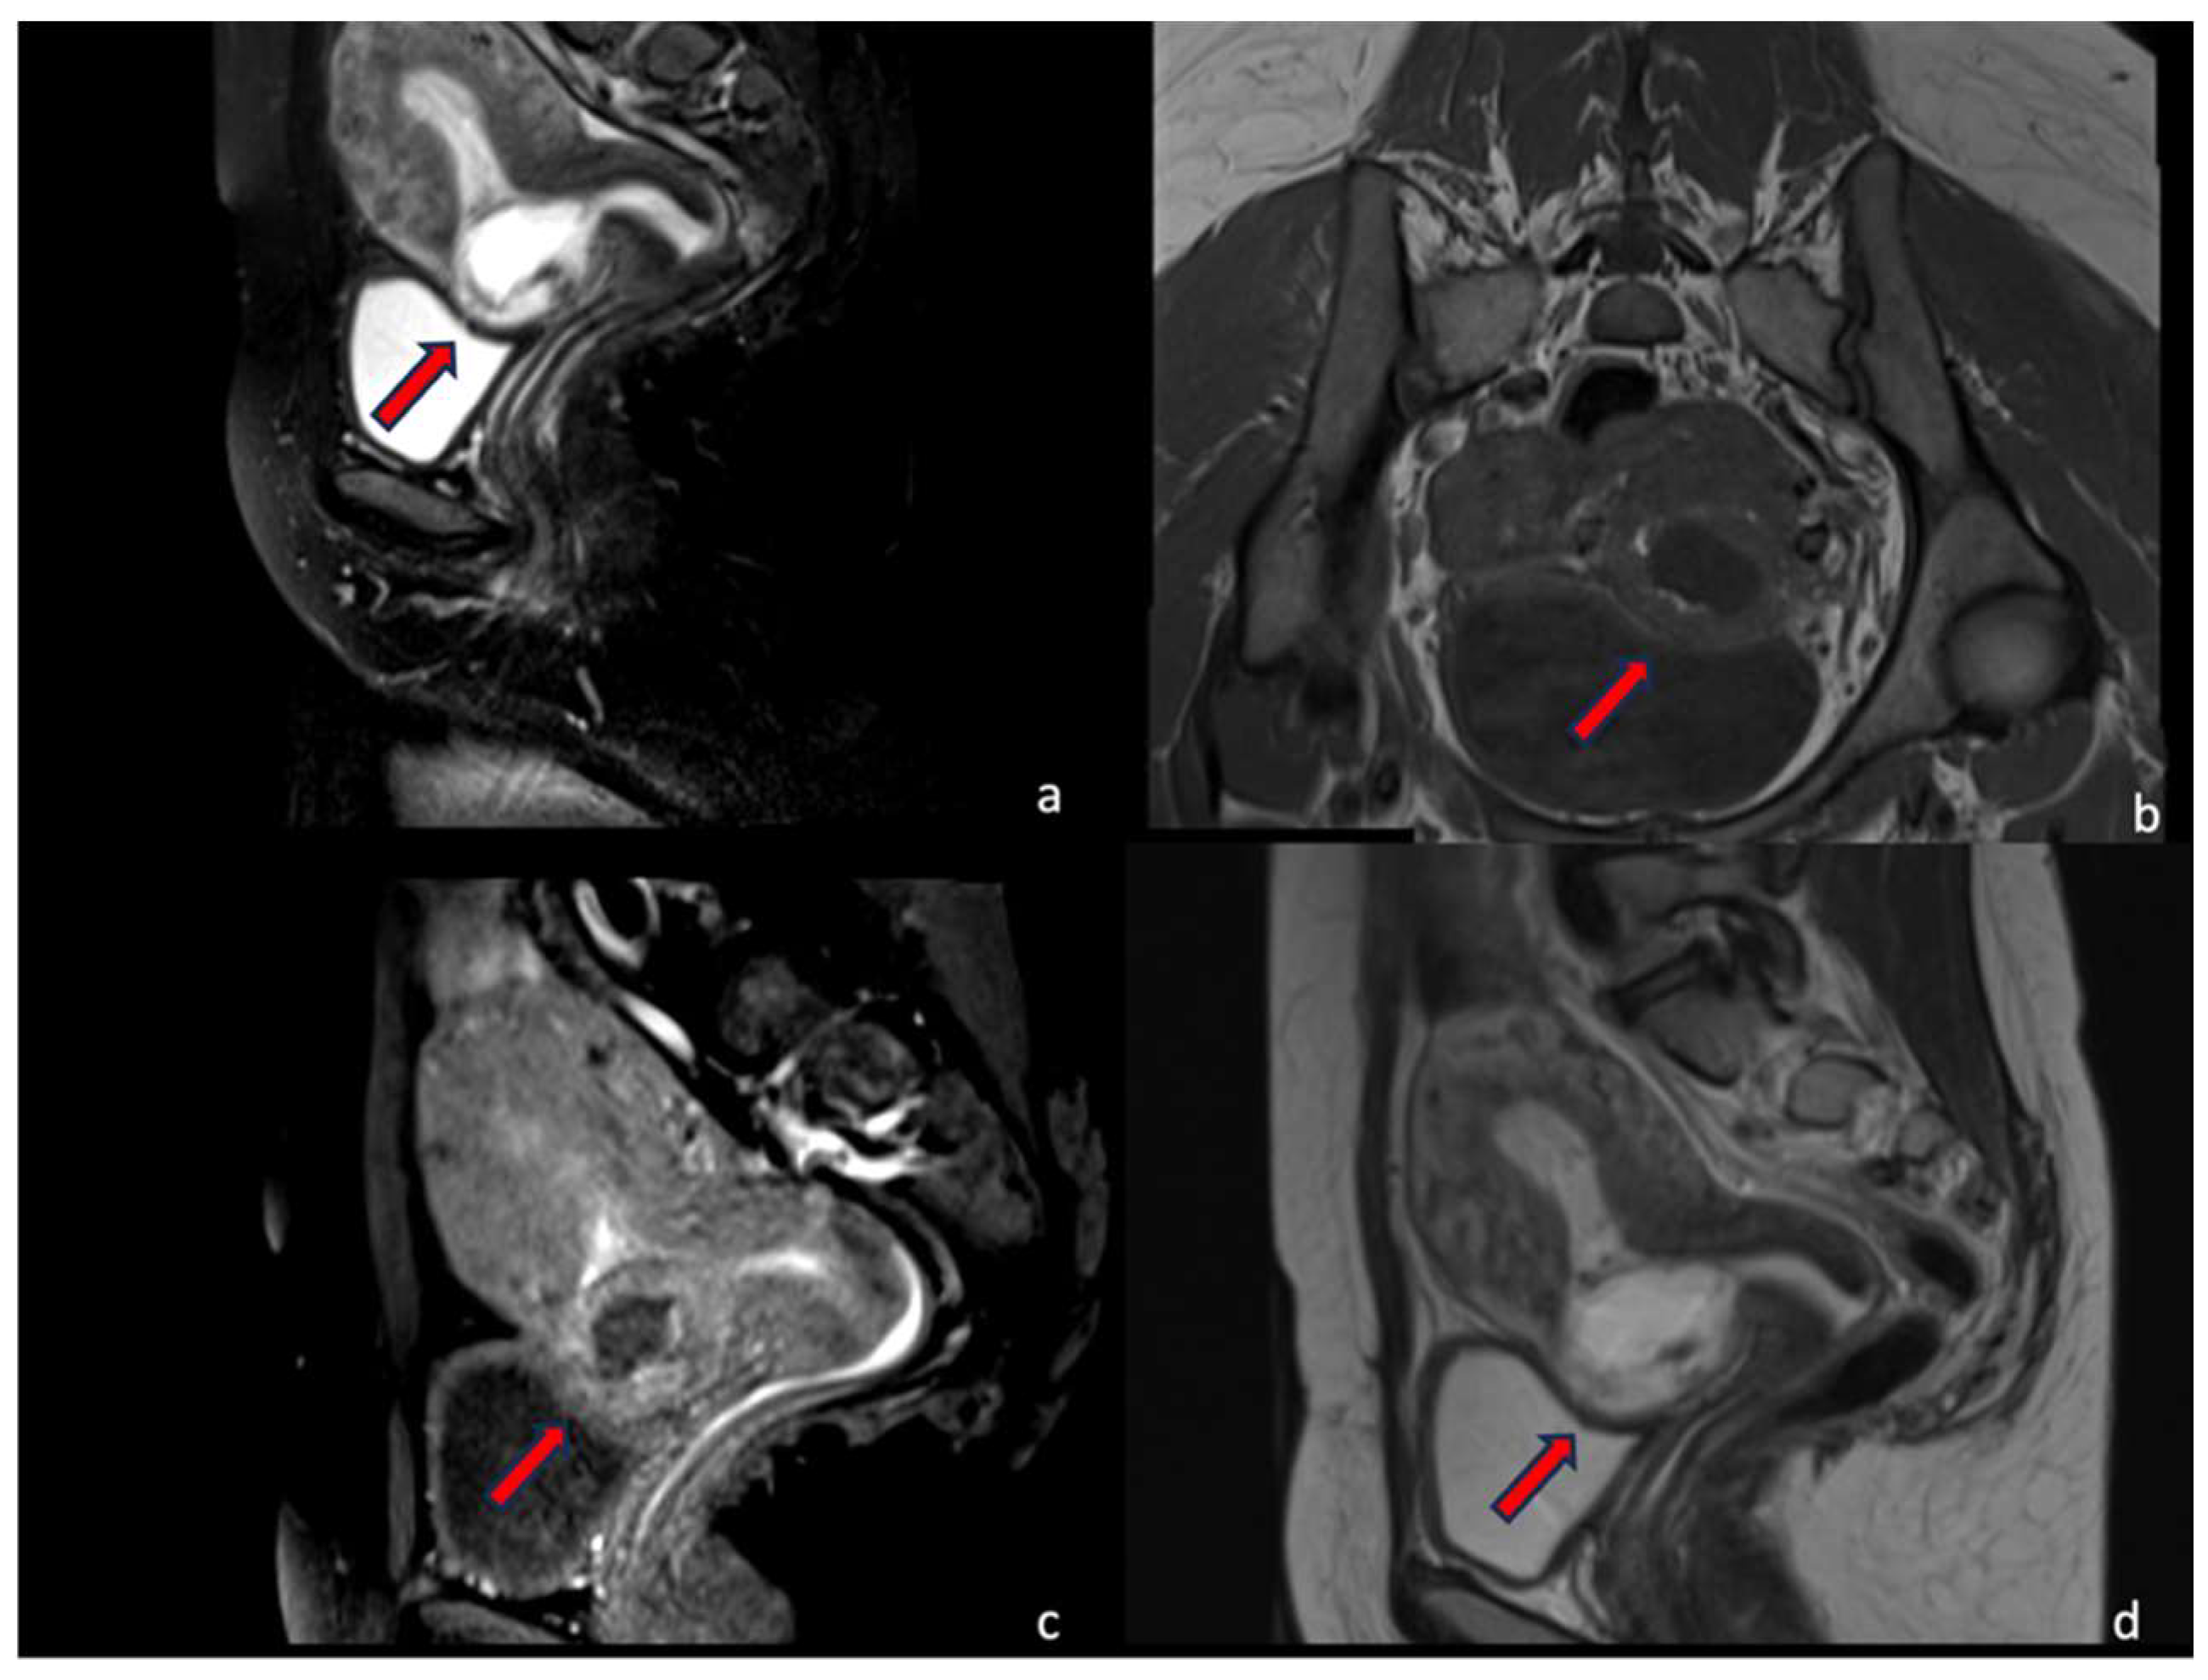

4.1.1. Case 1 (CSP Type I)

4.1.2. Case 2 (CSP Type II)

4.1.3. Case 3 (Low-Implanted Pregnancy)